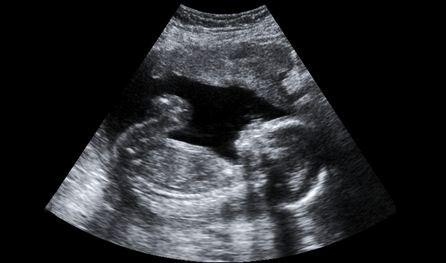

Az egyik legizgatottabban várt vizsgálat a gyermekvárás hónapjai alatt az ultrahang. Ennek a vizsgálatnak nemcsak komoly diagnosztikai jelentősége van, de betekintést nyújt a növekvő, várva-várt kicsi világába is, még akkor is, ha csak hagyományos vizsgálaton veszünk részt. Nincs is annál meghatóbb, mikor egy ilyen alkalommal először halljuk meg a baba dörömbölő, zakatoló szívverését.

Ám a vizsgálat után, a leleten olyan rövidítéseket találunk, amelyekből általában egy mukkot sem értünk. Mert hát mi is lehet az a BPD? Az alábbi listából mindenre fény derül.

A terhesség során végzett ultrahangos vizsgálatok leletén ezekkel a rövidítésekkel találkozhattok: